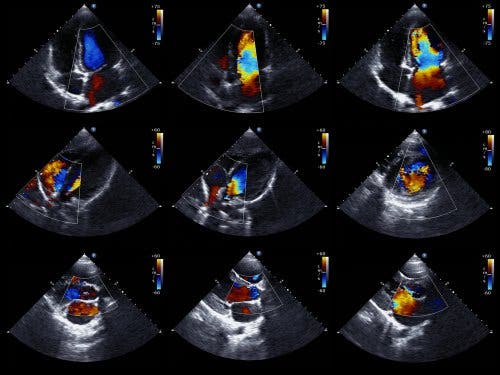

An echocardiogram is the preferred test to detect a pericardial effusion. It’s also called echocardiography or a cardiac ultrasound, and it’s a test that lets doctors see the structure of the heart and study its ability to pump blood.

The Doppler echocardiogram also lets doctors determine the exact speed of the blood flow from the heart. From a technical point of view, the two-dimensional and M-mode echocardiogram is the ideal technique for diagnosing, quantifying, and monitoring pericardial effusion.

Finding an absence of echoes between the epicardium and the lateral pericardium allows doctors to diagnose a pericardial effusion. Then, the cardiologist determines the size of the effusion based on the amount of space between the two layers of the pericardium.

We should note that there are basically two types of echocardiogram. There’s the transthoracic, in which a device is placed on the chest, over the heart, and it emits sound. And the transesophageal, in which the device is inserted into the digestive tract up to the esophagus. The latter provides more detailed data.